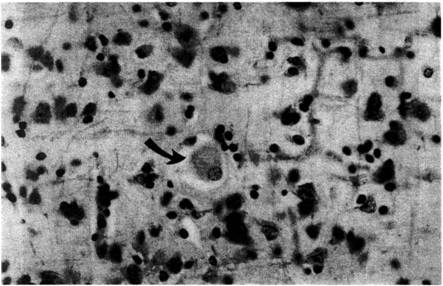

Болезнь Нимана-Пика Тип А: Симптомы и лечение

Раздел: Визуальный дайджест